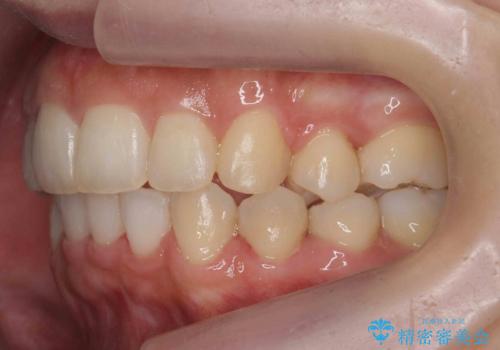

前歯がでている 最小限の抜歯で口を閉じやすく

- 出っ歯を主訴に来院。

上下のかみ合わせが1本分左右ともずれていました。

下顎がとても小さく後方位であるため、オトガイの閉口時のシワは完全になくすことは難しかったですが、前歯も大きく下がり満足していただきました。